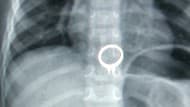

Un niño de 3 años se come un anillo de diamantes y se salva de una muerte segura

El pequeño jugaba con la joya cuando se la tragó. Los médicos tuvieron que hacer un procedimiento de emergencia para lograr extraerlo.